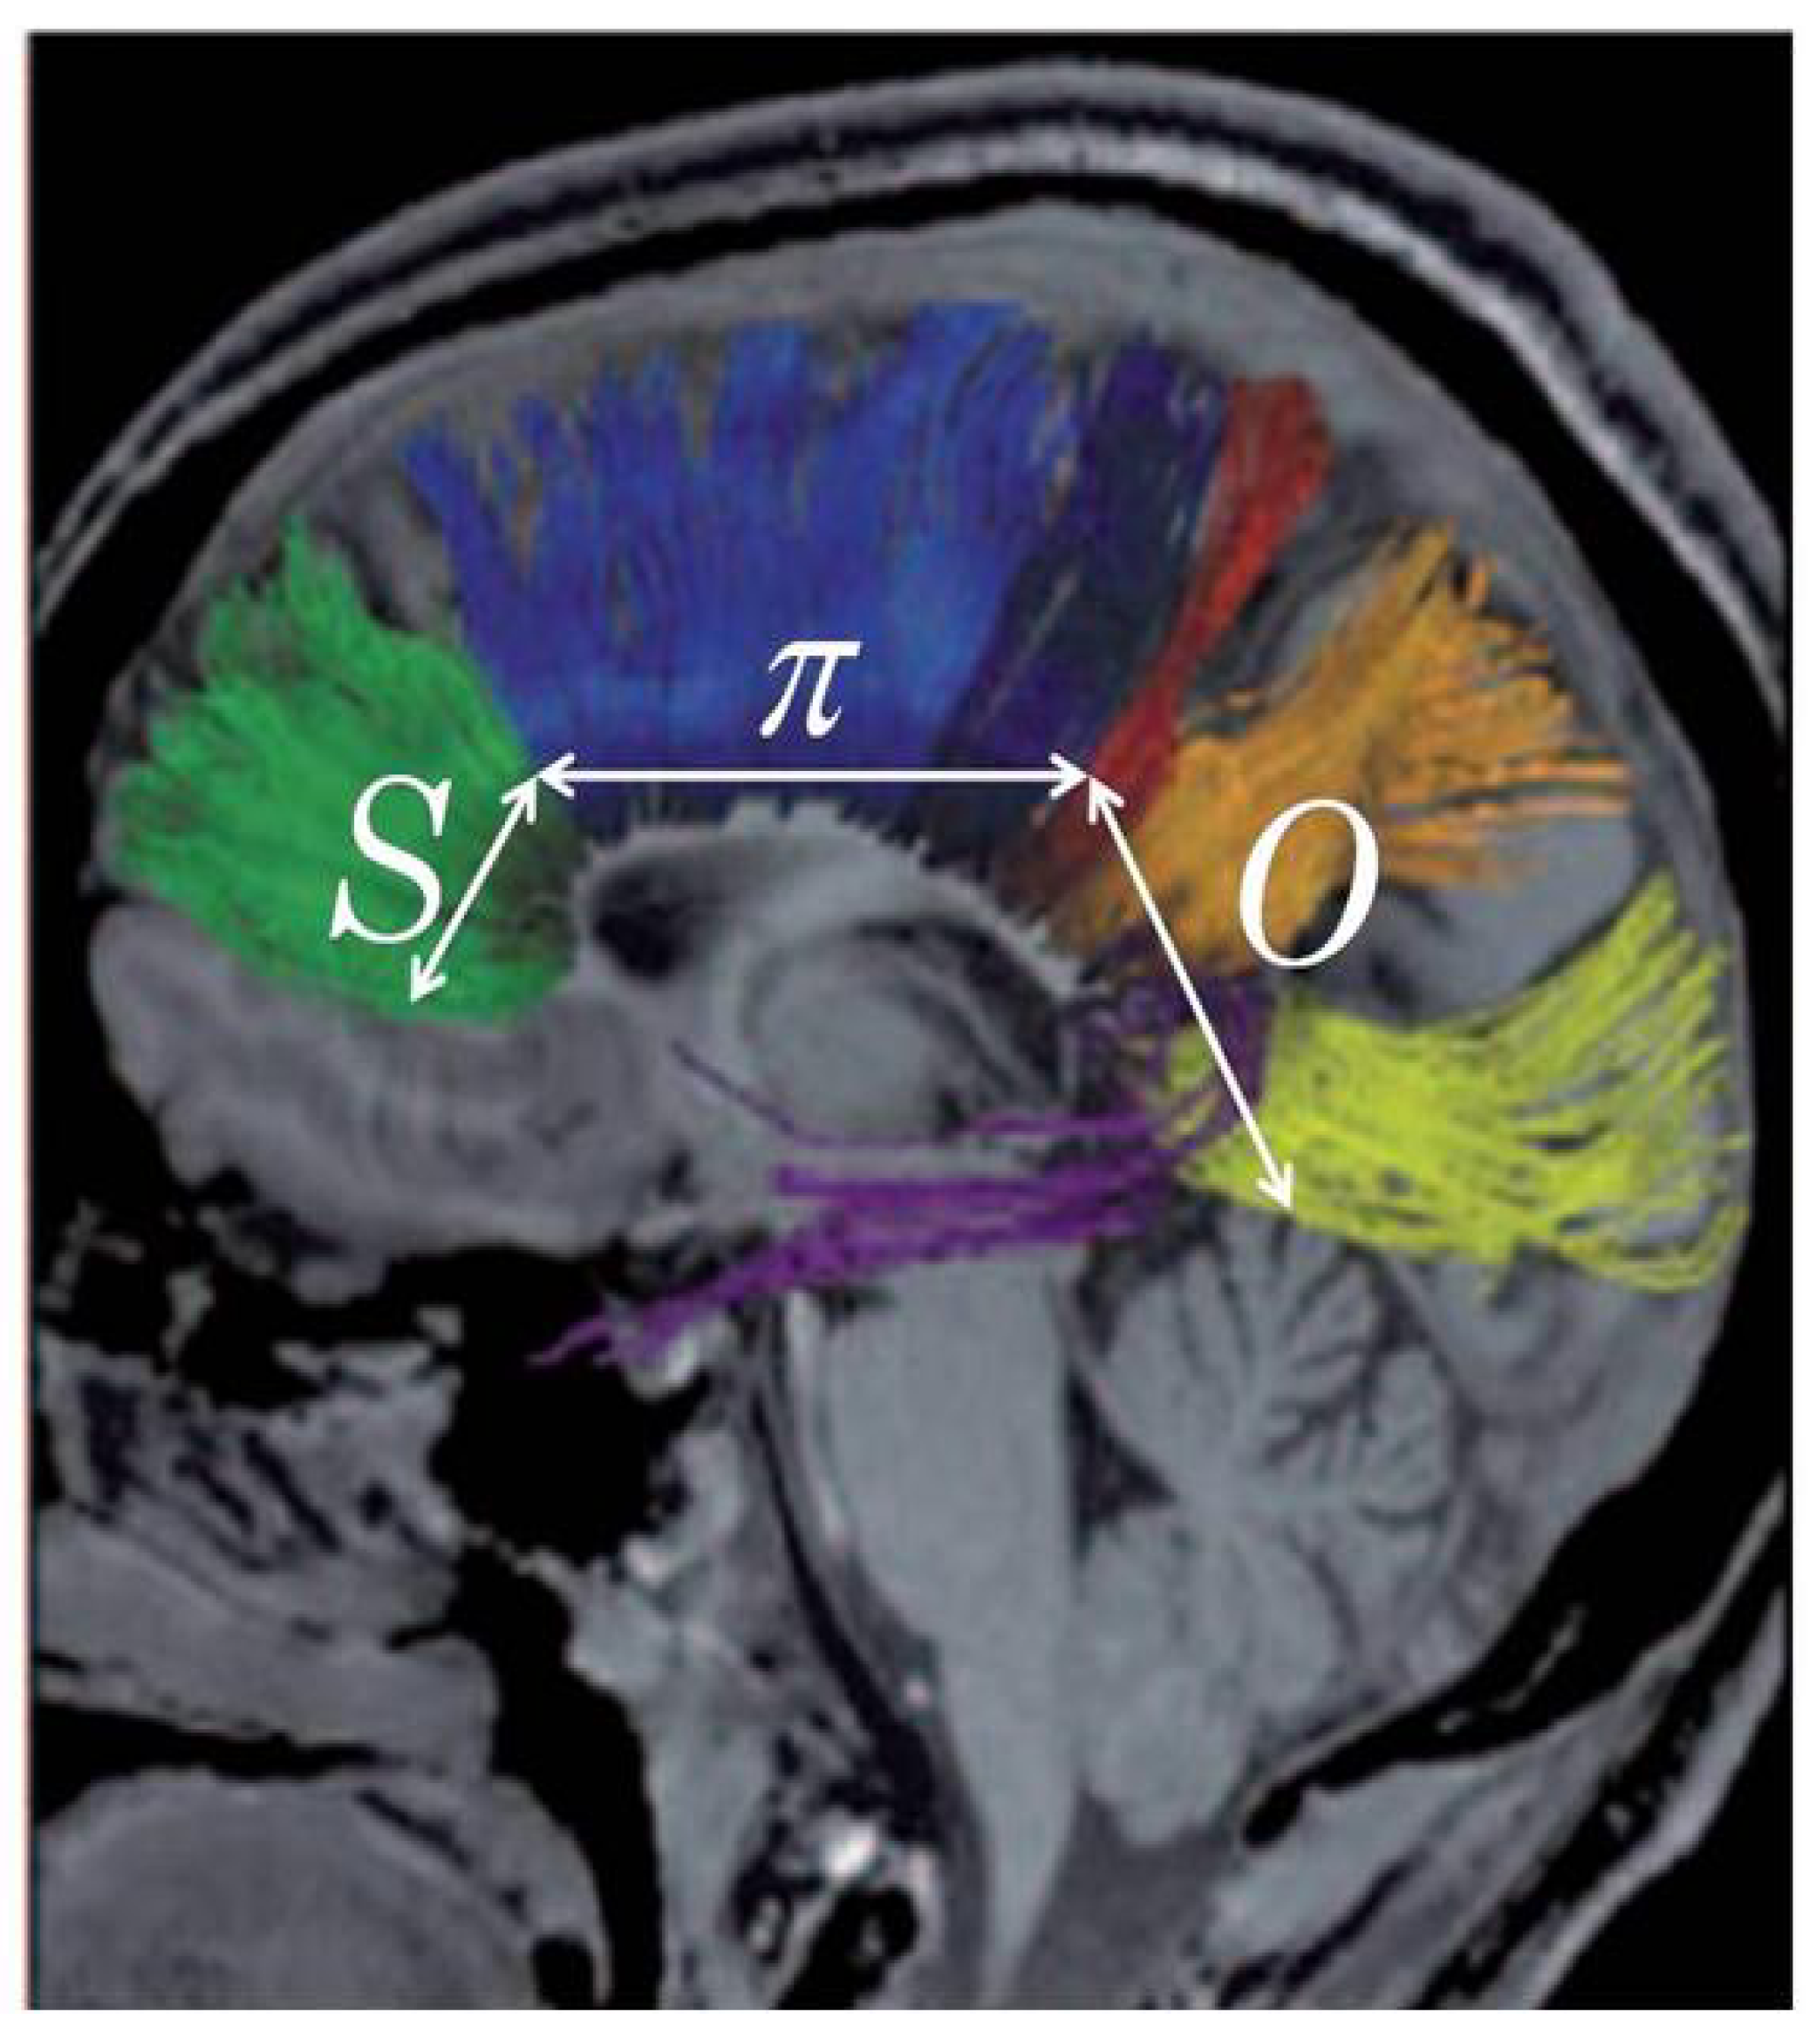

Furthermore, we must suppose that the development of the normal mapping of neurons through the corpus callosum must also reflect the same basic SπO formula as suggested in Figure 5. More specifically we must predict that the rostrum and genu (the bend) at the front of the corpus callosum should be associated with symbolic functions, S; the body of the corpus callosum should be associated with articulate and tactically complex motor sequences (as seen in speaking, writing, typing, and signing), π; and the basic sensory functions involved in constructing icons of objects should be associated with the posterior portion of the corpus callosum, O.

Figure 5.

The pragmatic mapping relation (in white lettering) hypothesized in the neuroarchitecture of the corus callosum (colored in green).

Until recently, with the development of diffusion tensor magnetic resonance imaging (dMRI)—e.g., see Paul, et al. [57] as well as Hofer and Frahm [58]—the inferences of Figure 5 could only be tested against symptomatic observations of persons with focal lesions in the corpus callosum. However, with dMRI it has become possible to map the estimated 190 million axons extending from the neuronal bodies extending from various regions of the cortex through the corpus callosum to the highest level of the neurons of the opposite hemisphere of the cortex as shown in Figure 6. The mapping actually found is indeed consistent with the formula, SπO. Also, as we should expect, focal lesions in the corpus callosum produce symptoms consistent not only with inferences at the global level of neuroarchitecture suggested in Figure 3, but also with considerably more specific predictions flowing from the hypothesized architecture of the corpus callosum suggested in Figure 5 and borne out in Figure 6.